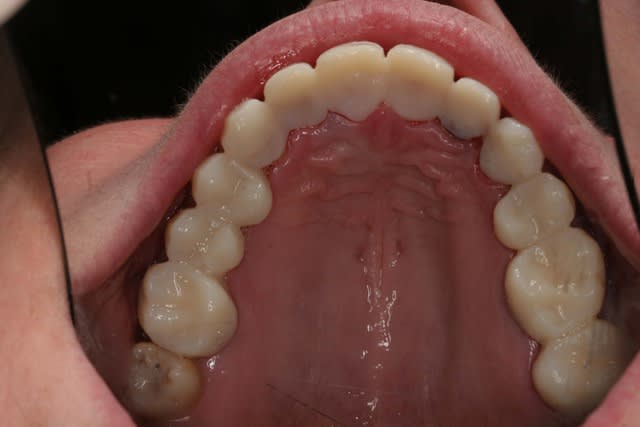

Voila la suite pour le maxillaire, le wax est fait sur arti en fonction de l'OIM obtenue après ortho. seule la 27 restera intacte.

Préparation des molaires pour permettre des RTE sous digue à travers les provisoires, retrait des anciennes couronnes et ancrages sur les 12, 15 et 25 endo satisfaisantes (couronnes ayant plus de 30 ans pour certaines!!!.

Tailles parallèles pour zircone 13 à 23 seront solidarisées pour éviter une migration post ortho.

Gingivectomie légère à la fraise à biseau pour harmoniser les collets, mais l'ortho a permis d'énormément faciliter ce travail.